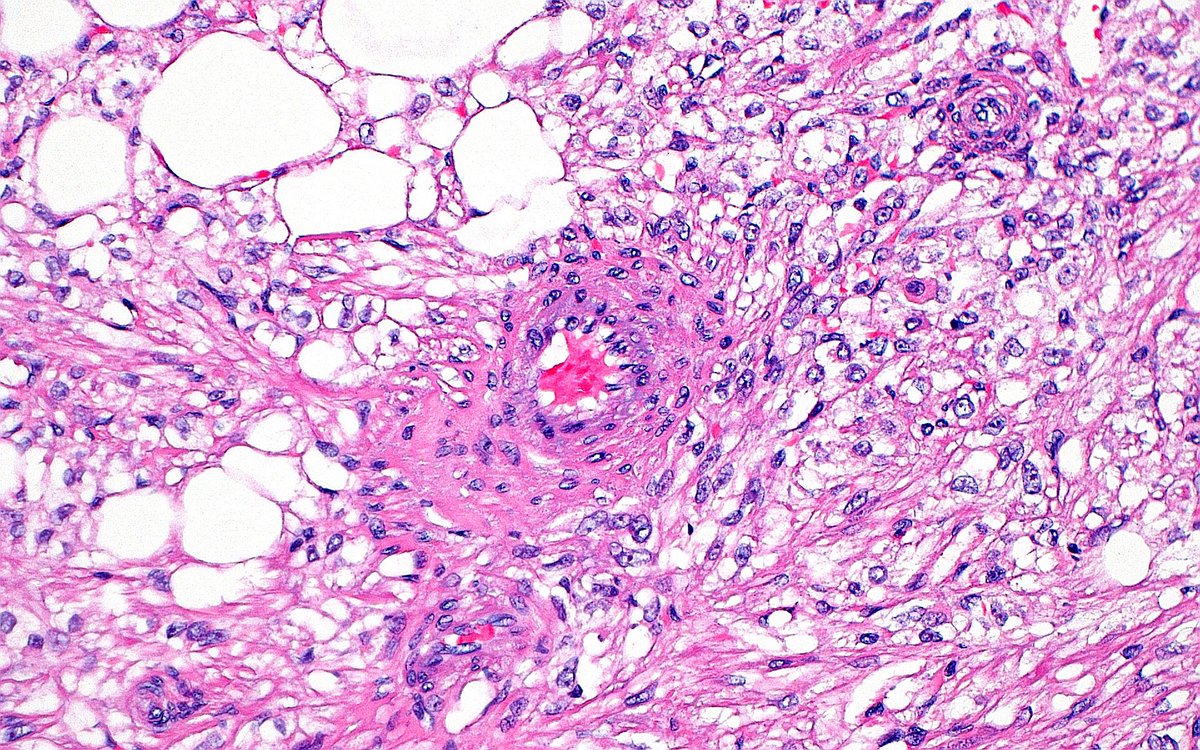

DFSP of the vulva - an uncommon location. These are low-to-intermediate grade sarcomas that are locally aggressive and often recur. Mainstay of treatment is surgery. Metastasis is rare. CD34+, S100-, Desmin-, SMA-, CK-, STAT6- #vulva #pathtwitter #gynpath #dermpath #BSTPath

DFSP of the vulva - an uncommon location. These are low-to-intermediate grade sarcomas that are locally aggressive and often recur.  Mainstay of treatment is surgery. Metastasis is rare.  CD34+, S100-, Desmin-, SMA-, CK-, STAT6-